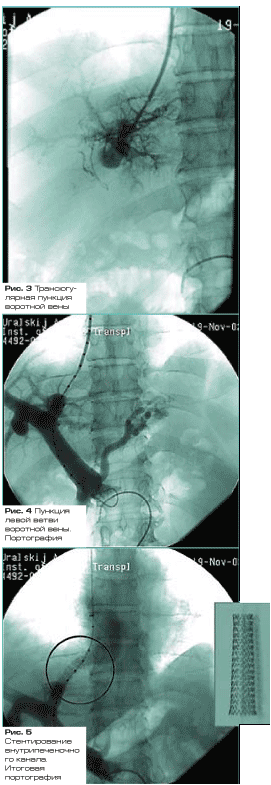

Стандартная методика выполнения TIPS состоит из следующих этапов:

· производят пункцию правой внутренней яремной вены, катетер проводят в правую ветвь печеночной вены;

· затем производят пункцию ветви воротной вены через стенку печеночной при помощи специальной пункционной системы (рисунки 3, 4);

· затем в воротную вену проводят баллон-катетер, которым производят дилатацию канала печеночной паренхимы;

· после этого новообразованное портокавальное соустье “армируют” внутрисосудистым стентом.